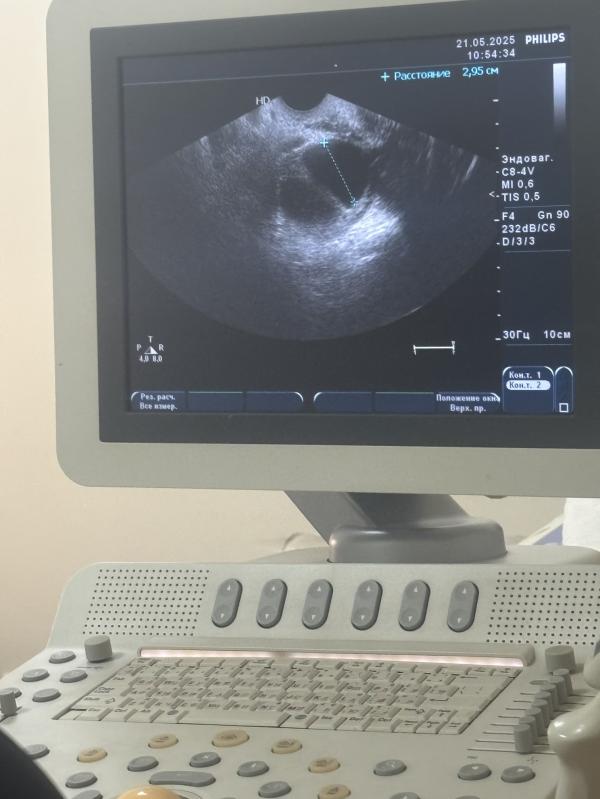

Левый яичник сказали прям очень хороший 8дпо с желтым телом 🫣сказала может и не придут мес может будет беременность

Отличный эндометрий 10 не плохо.. С 7-8 уже норм, с 9 отлично

Жёлтое тело отличное